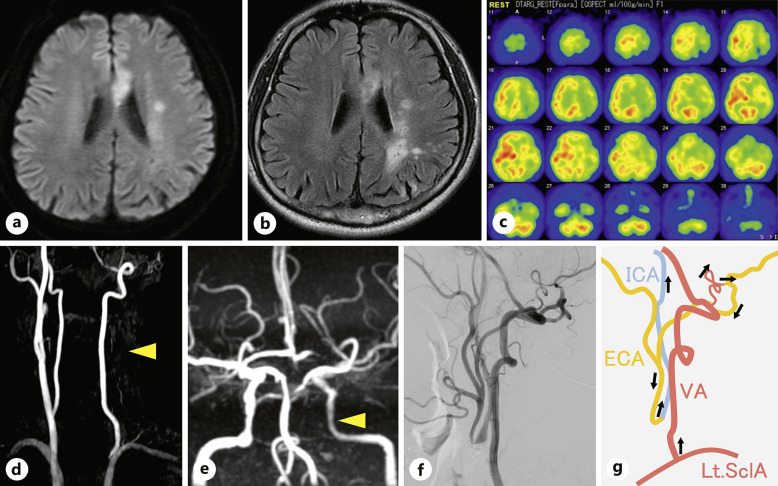

简介:颈总动脉闭塞(CCAO)虽然罕见,但可引起缺血性神经功能障碍,可通过血运重建术治疗。虽然已经提出了几种CCAO旁路入路,但对手术血运重建入路及其功能结局尚未达成共识。在此,我们报告了一例Rile's 1A型CCAO,其中使用桡动脉移植物(RAG)进行锁骨下动脉(SclA)-颈内动脉(ICA)旁路治疗可立即恢复认知功能并成功预防缺血性中风。病例描述:58岁男性,右侧无力反复发作。脑磁共振成像显示多发脑梗死。数字减影血管造影证实左侧CCAO,左侧ICA及同侧颈外动脉无顺行血流。从左巩膜到左颈ICA采用左RAG进行搭桥,巩膜和ICA之间的锁骨上吻合无移植物血管扭结。术后无神经功能缺损,认知功能得到改善。结论:RAG旁路是CCAO的合理治疗选择。CCAO血运重建术可预防缺血性脑卒中,改善认知功能。

Introduction: Although rare, common carotid artery occlusion (CCAO) causes ischemic neurological dysfunction, which can be treated by revascularization. Although several bypass approaches for CCAO have been suggested, no consensus on the surgical revascularization approach and its functional outcome have been reached. Herein, we present a case of Rile's type 1A CCAO in which a subclavian artery (SclA)-internal carotid artery (ICA) bypass using a radial artery graft (RAG) resulted in immediate recovery of cognitive function and successfully prevented ischemic stroke.

Case description: A 58-year-old man presented with recurrent episodes of right-sided weakness. Brain magnetic resonance imaging revealed multiple cerebral infarcts. Digital subtraction angiography confirmed left CCAO and no anterograde blood flow in the left ICA and ipsilateral external carotid artery. A bypass was performed from the left SclA to the left cervical ICA using a left RAG, and supraclavicular anastomosis between the SclA and ICA was performed without graft-vessel kinking. Postoperatively, no neurological deficits were observed, and his cognitive function was successfully improved.